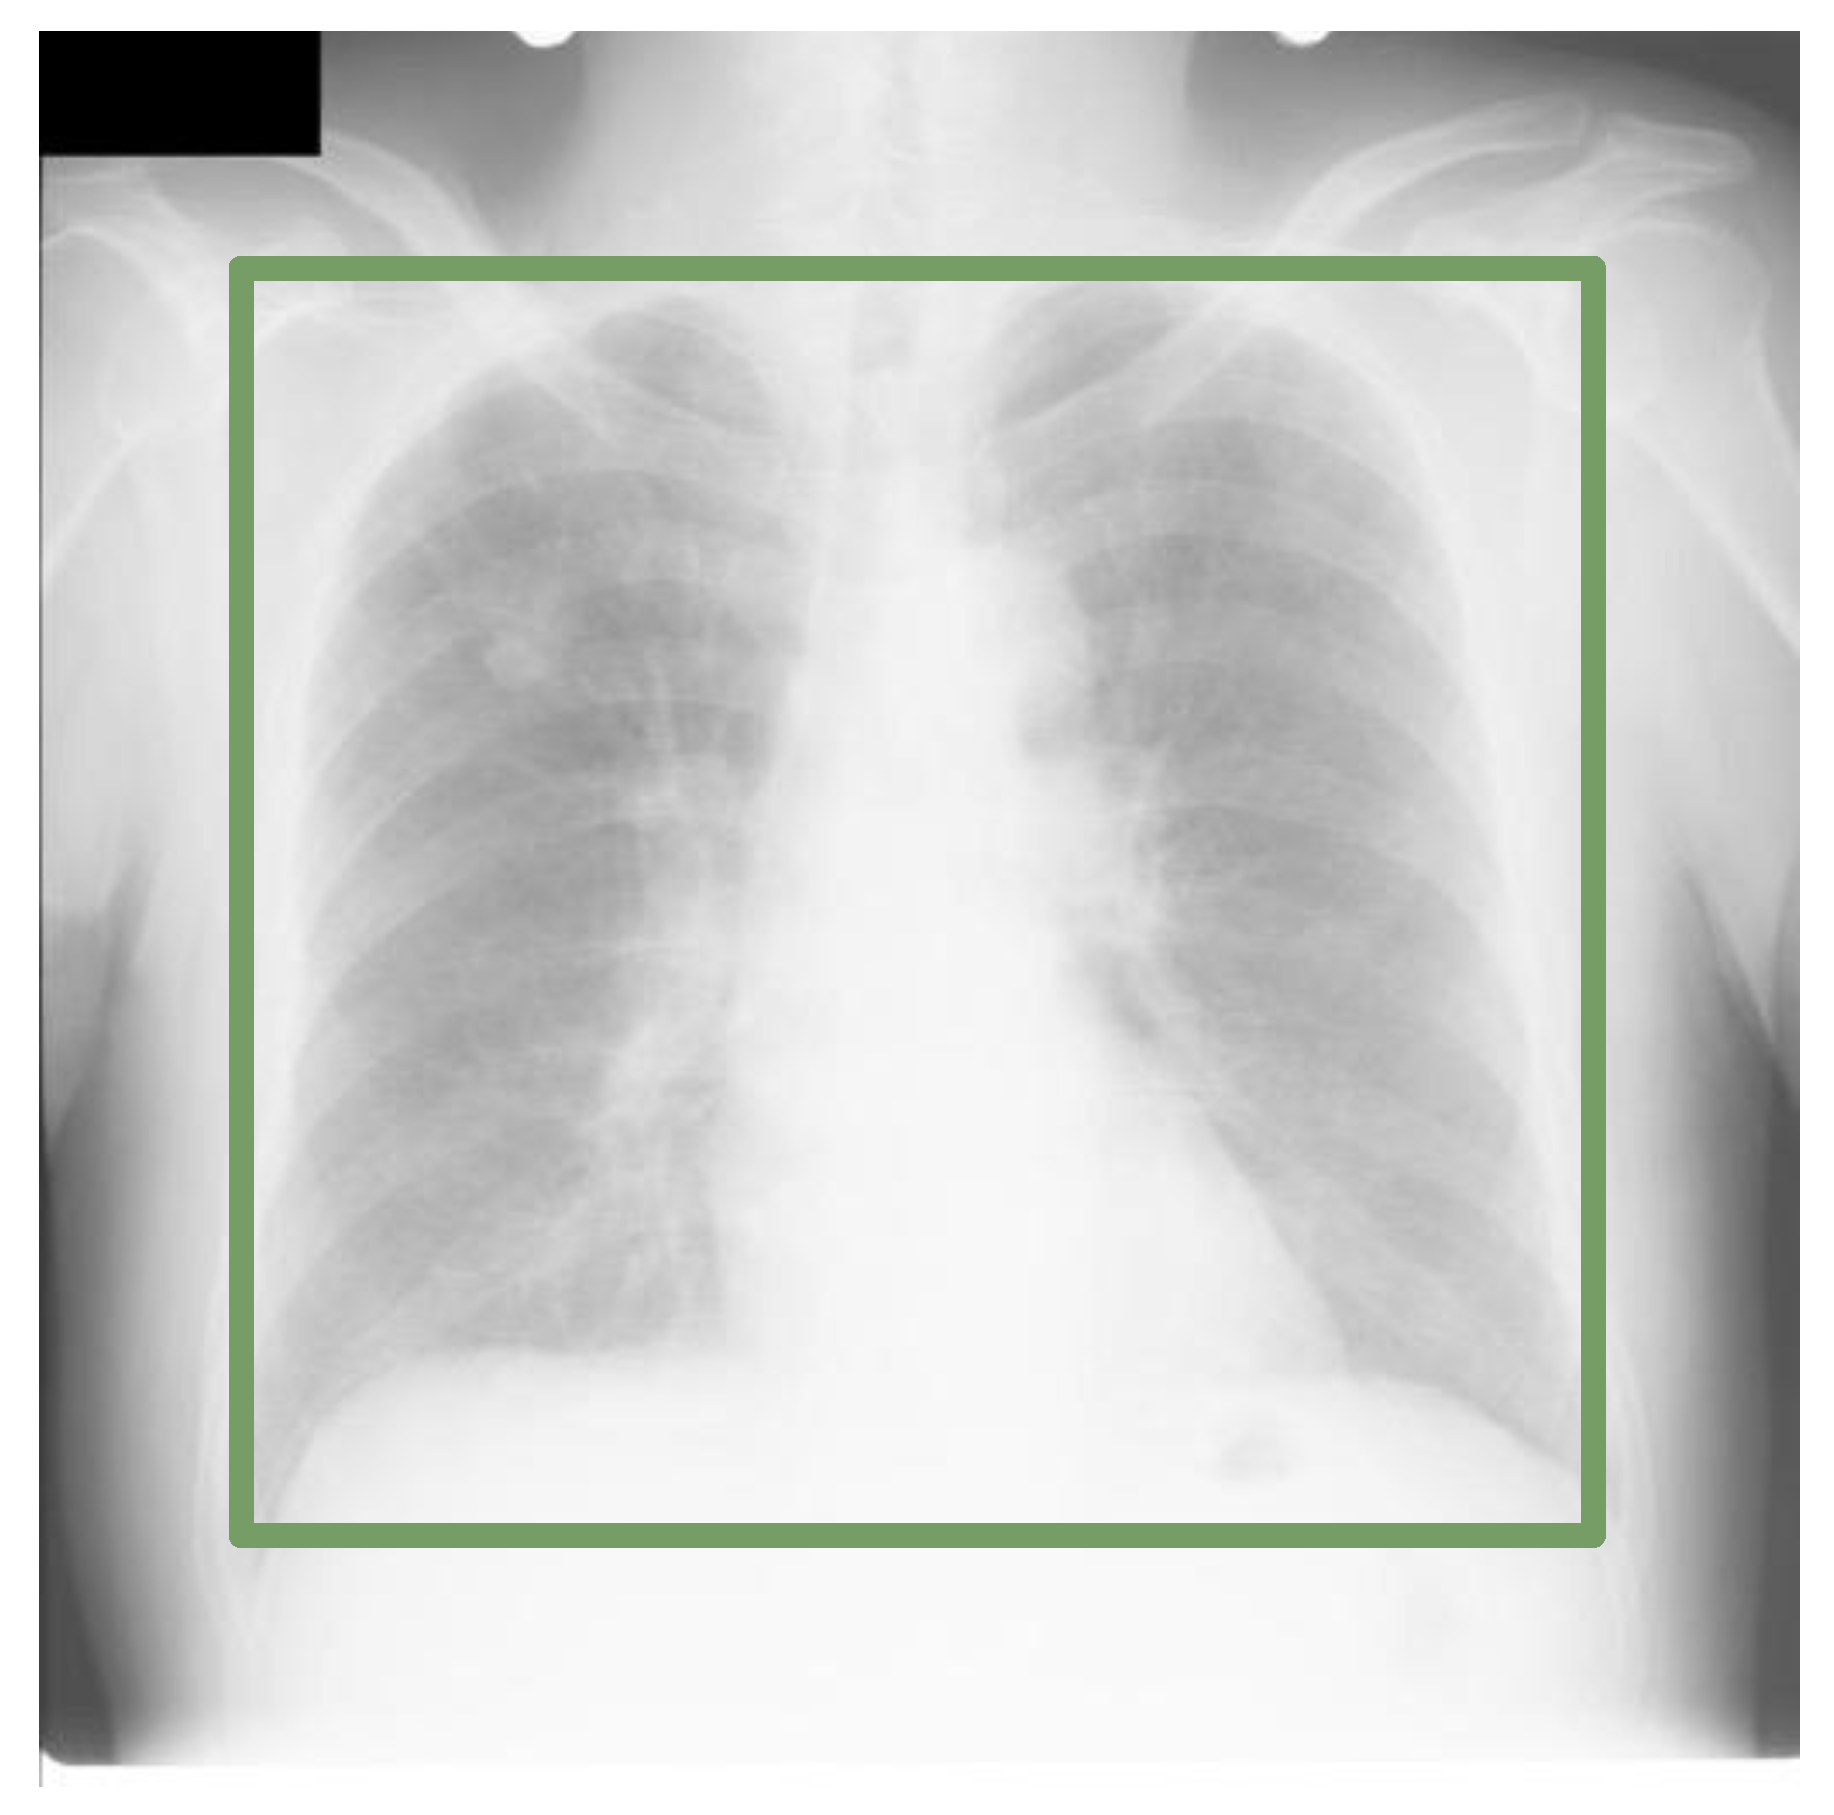

Cross Dataset Analysis of Domain Shift in CXR Lung Region Detection

2.1. Datasets